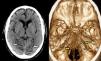

Síndrome de Anton con presentación atípica

Anton's syndrome with atypical presentation